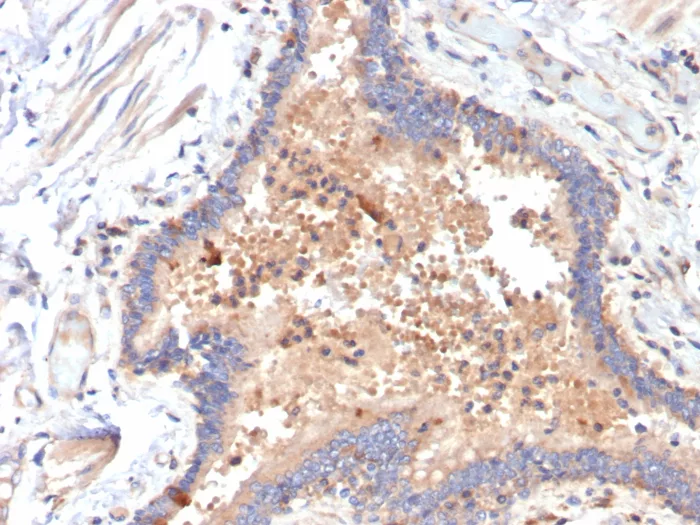

Formalin-fixed, paraffin-embedded human COVID positive lung stained with IL-6 Mouse Monoclonal Antibody (IL6/4642) at 2ug/ml. HIER: Tris/EDTA, pH9.0, 45min. 2°C: HRP-polymer, 30min. DAB, 5min.